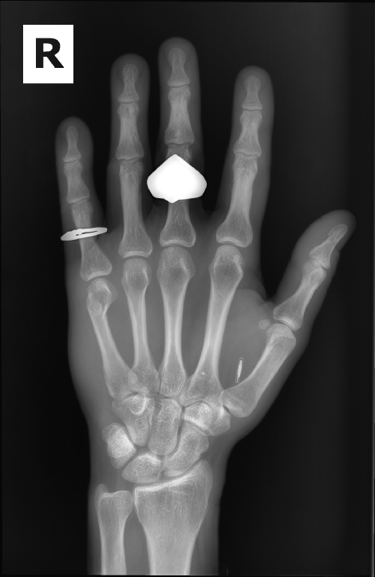

In 2015 at the DEFCON hacker conference in Las Vegas, NV I was at the Dangerous Things table and decided to buy one of their implantable RFID kits. You can find them here.

It took a while to find someone that would help me inject it. My roommate at the time was a nurse and wouldn't and I didn't really think at the time it was a good idea to do it myself but would probably give it a try now if I needed to. Eventually, one of my friends who is an ER doctor stepped up and on Christmas Eve got it in there.

The story of how I got the x-ray or at least the whole scenario was kind of funny. I broke my pinky somehow at my friend's house in Oklahoma in the fall of 2023. When I went to the doctor they did an x-ray of my hand. I have a few metal parts in my head and then told them I got into a fight and thought I may have hurt some implants in my head. Not really but I just wanted these X-rays.